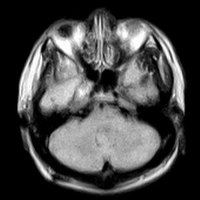

2.MR表現:

①腫物常跨越中後顱窩,典型者呈啞鈴狀。

②中顱窩三叉神經瘤壓迫鞍上池與海綿竇,後顱窩三叉神經瘤壓迫橋小腦角與第四腦室。

③腫瘤T1加權為低或等信號,T2加權為高或等信號。

④增強後多數明顯均一強化,少數囊變者環形強化。

⑤病灶周圍一般無水腫。